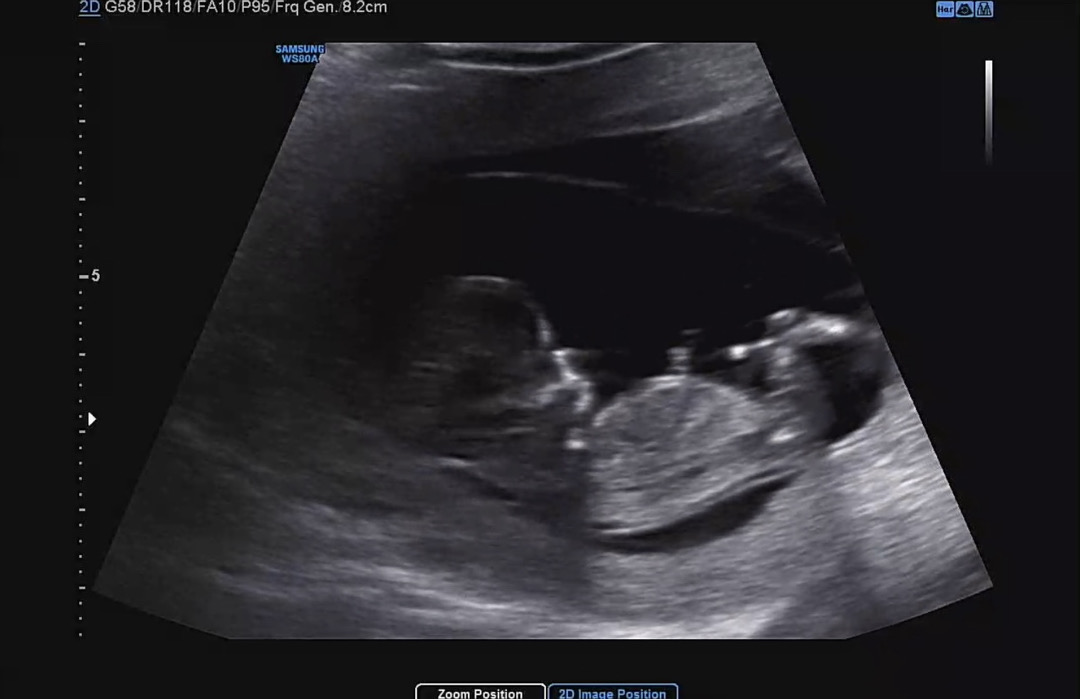

11주 6일차 아이 각도법 봐주세오!

각도법 고수님들! 저희 아기 성별 유추해주세요!✨🥹🩵